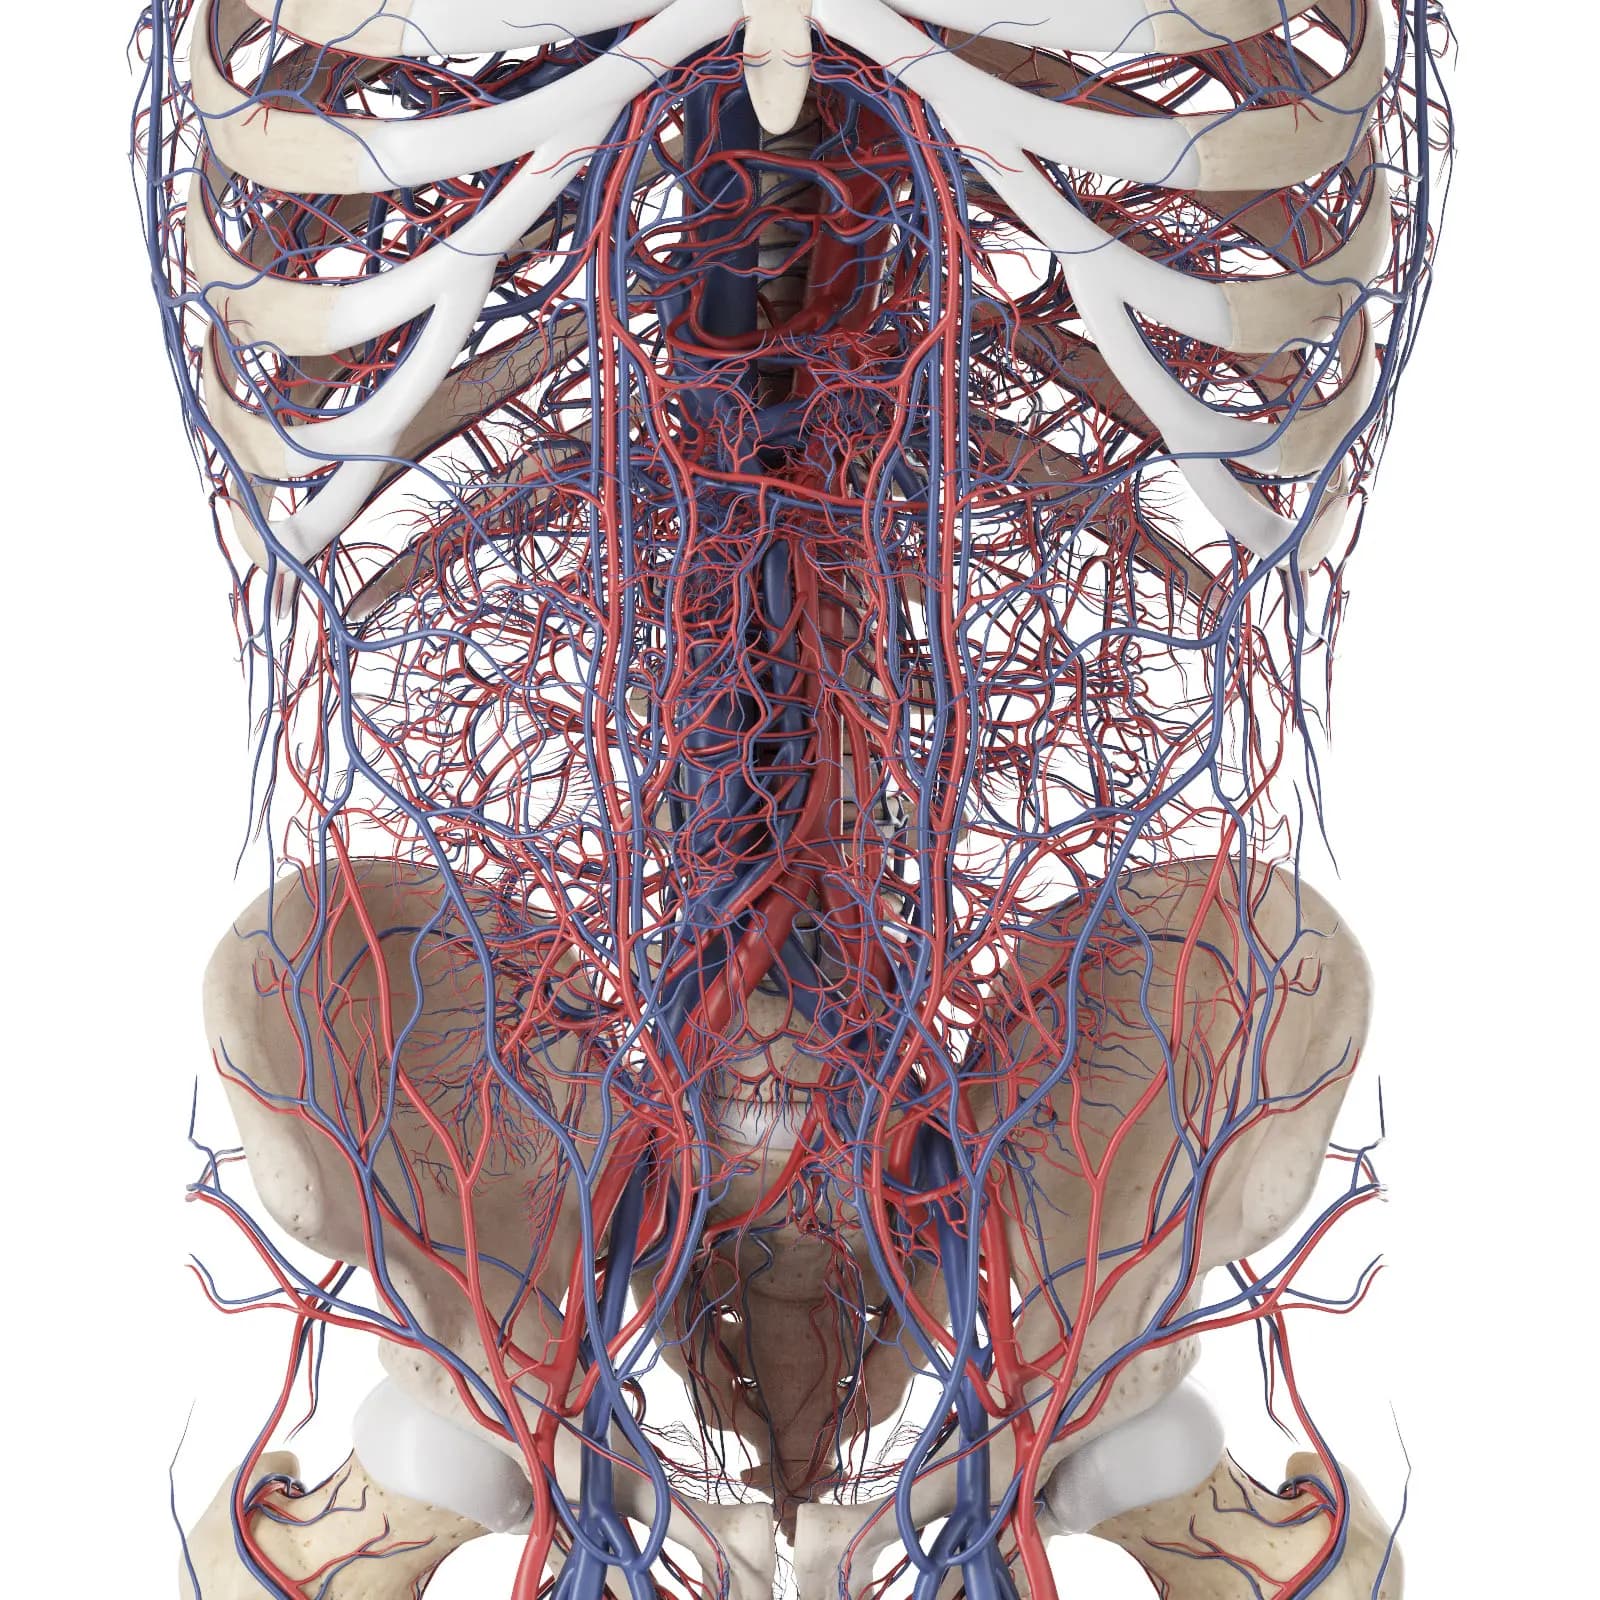

3d Rendered Medical Illustration Of The Vascular System Of The Back

3d Rendered Medical Illustration Of The Vascular System Of The Abdomen